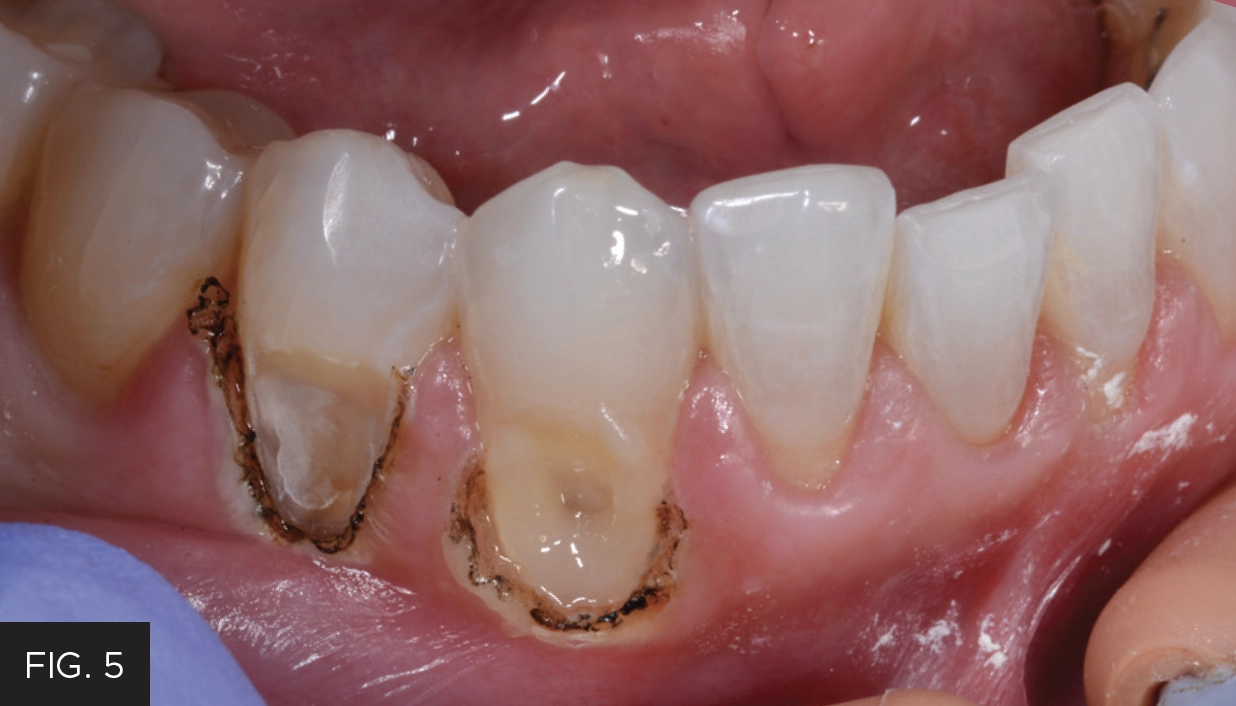

When using a laser, the laser beam is always directed away from the eyes and should always utilize the minimum power setting necessary to accomplish the procedure. If the laser tip drags while the laser is in active mode and is moving across the tissue, the power is too low. Simply increase the power as needed for the smooth removal of the tissue. On the other hand, if there is excess burning or blackening of the tissue, this is an indicator that the power level is too high. In this case, the Bluewave laser was set at a preset power setting of one (1) watt. (FIG. 3)